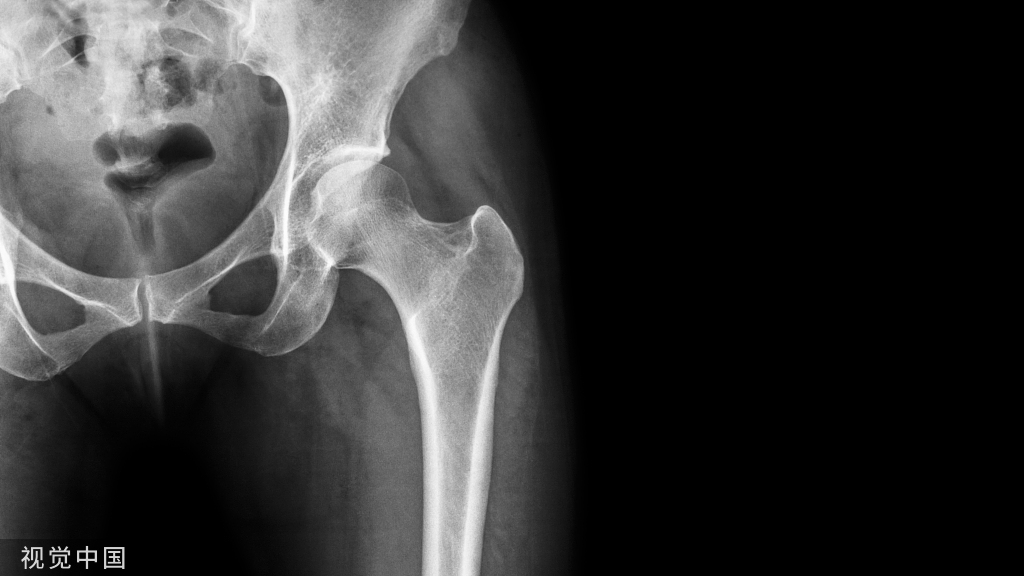

颈干角和前倾角最能体现髋关节的结构功能特征。

①颈干角:股骨颈与股骨干纵轴所形成的倾斜角为颈干角或内倾角。正常范围为110°~140°成年时平均为127°。 超过此角度的变形成为髋外翻(caxa valga),小于此角度者称之为髋内翻(coxa vara)。

②前倾角:股骨颈的轴线与股骨内外髁的髁间连线间有一向前扭转的角度,称为前倾角,成人一般不超过10°~12°,正常值在正常值在12°~15° 。

股骨上端的骨小梁系统

股骨头上端主要形成四组骨小梁,其排列方向沿股骨的主应变方向(有三组抗压骨小梁群基本上平行于股骨长轴方向,交织着由下方向上方走行,以保证股骨的强度和韧性,对抗体重的的重力;而主抗张骨小梁群的骨小梁则起到对抗横向张力的作用),从而最大限度地减少剪力:

控制骨骼重塑过程的原则称为沃尔夫定律(wolff’s law)

机械应力与骨组织间存在一种生理平衡。在平衡状态,骨组织的成骨细胞和破骨细胞的活性是相同的。当应力增大时,成骨细胞活跃,引起骨质增生,承载面增大,使应力下降,达到新的平衡;当应力下降时,破骨细胞再吸收加强,骨组织量下降,使应力增加。因此骨能通过改变它的大小、形状和结构以适应力学的需要进行功能重建。

股骨头、颈处骨小梁的排列方向明显遵循沃尔夫定律:当压应力或张应力施加在骨骼上时,骨骼的骨小梁会根据需要自行排列生长,以适应承重的需要。经常运动会使得骨骼受力增加,使骨量增加,骨质坚硬;而长期不运动、骨骼不受力,则会造成骨量减少,骨质疏松。